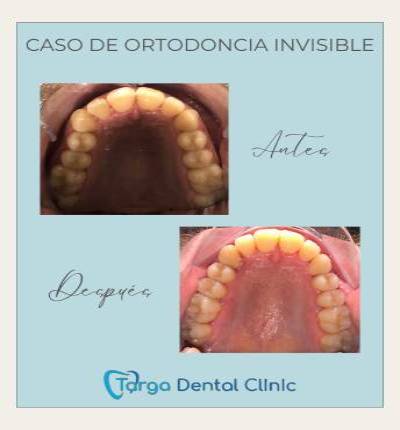

Ortodoncia y Odontopediatría

Ofrecemos tanto ortodoncia invisible con alineadores como ortodoncia fija con brackets.

Evaluamos cada caso y te recomendamos el más adecuado para ti. También ortodoncia para los más pequeños y los pacientes en crecimiento.